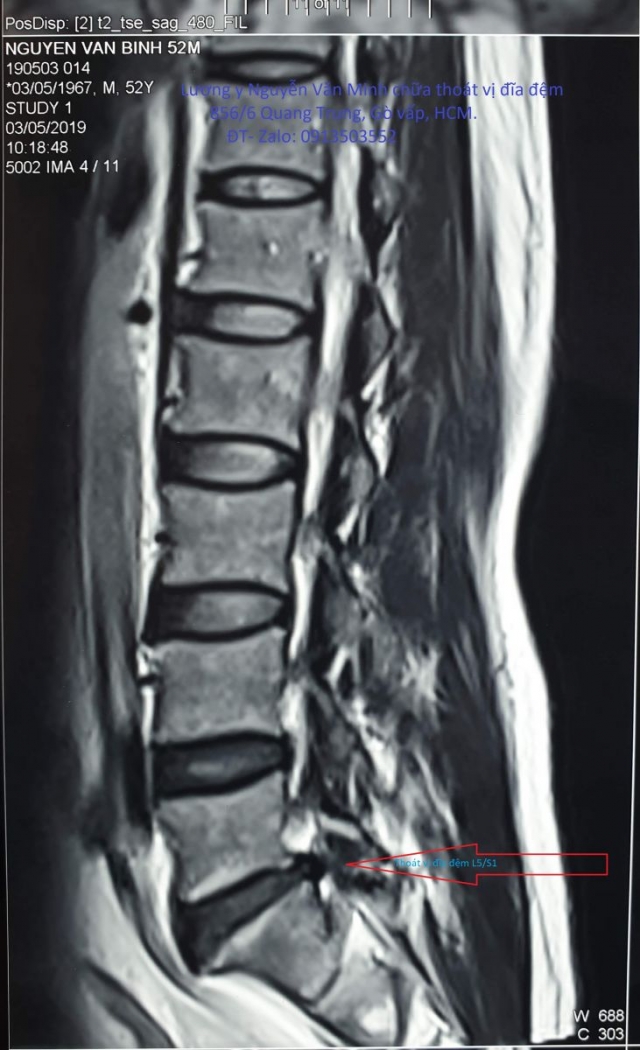

Hình ảnh thoát vị đĩa đệm

Hình ảnh thoát vị đĩa đệm, hình ảnh lồi đĩa đệm, thoái hóa đĩa đệm mất nước.v.v. Đây là những hình ảnh chụp lại trên phim cộng hưởng từ MRI. Kèm theo những kết luận của bác sĩ chuyên khoa cột sống, được Lương y Nguyễn Văn Minh cập nhật liên tục để bạn đọc tham khảo.❮ đọc tiếp ❯

Thoát vị đĩa đệm L4-L5, L5-S1, chèn ép rễ thần kinh Thoát vị đĩa đệm L4-L5 ra sau #5mm, chèn ép bao màng cứng, gây hẹp lỗ liên hợp hai bên, chèn ép rễ thần kinh L4, L5. Thoát vị đĩa đệm L5-S1 trung tâm ra sau #5mm, chèn ép mặt trước bao màng cứng, gây hẹp lỗ liên hợp hai bên, chèn ép rễ thần kinh L5, S1.❮ đọc tiếp ❯